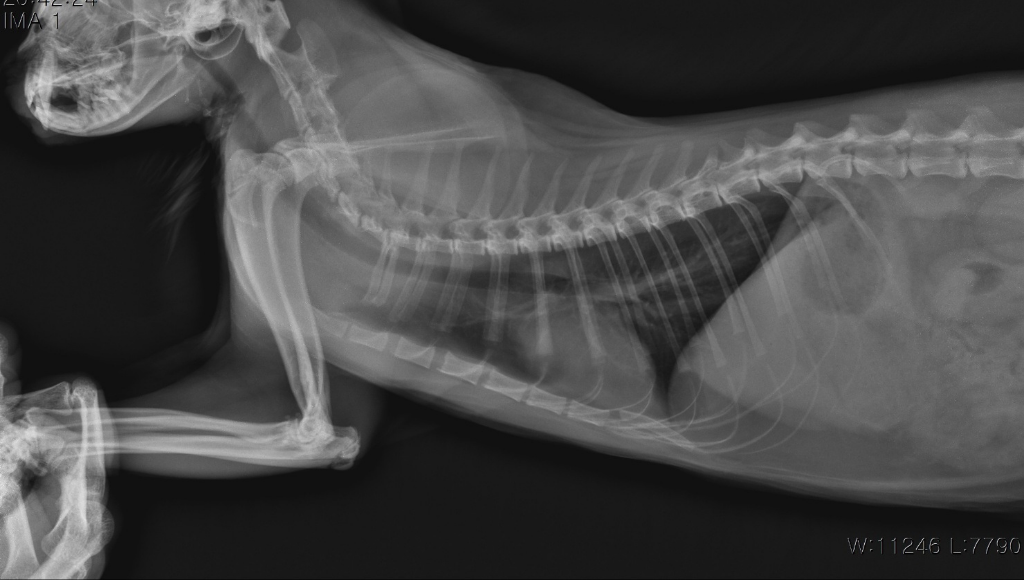

병원에서 복막염의심80% 이라고 합니다

그저께 열이 40.3도 올랐고

하루입원해서 열은 그대로 였습니다

식욕부진, 무기력 합니다 무게는 4.4에서 4kg 빠지다가 지금 4.1입니다

설사,구토는 한번도 안하고 오히려 소변만 보고 대변을 안보고 있습니다 그래서 저는 장폐색 같은거 조금 의심이 생겨서 가능성은 있나요? 초음파검사로 하면 알 수 있나요?

3살 미만에 소화기 증상 그리고 혈액검사상 글로블린이 높은 경우 고양이 전염성 복막염을 생각해볼 수 있습니다.

보통 초음파까지 확인을 해봐야 알겠지만, 복수가 있으면서 복수가 짚처럼 반투명하게 노란 복수양상은 거의 고양이 전염성 복막염입니다.

"설사,구토는 한번도 안하고 오히려 소변만 보고 대변을 안보고 있"는것은 장폐색의 주 증상과 정 반대라고 볼 수 있습니다. 장폐색이 있으면 주로 폭발적 구토가 유발되기 때문이지요. 의심이 된다면 복부 초음파 검사를 통한 확인이 가능한 상태이니 복부 초음파 검사를 받아 보시기 바랍니다.

혈액검사 결과와 방사선 검사상 위장관의 대비도 감소 등을 볼때 심각한 수준의 장염이 또다른 원인이 될 수는 있으나 복막염 가능성이 매우 높으니 주치의와 상의하에 복막염 확진 검사를 진행하시는걸 추천합니다.